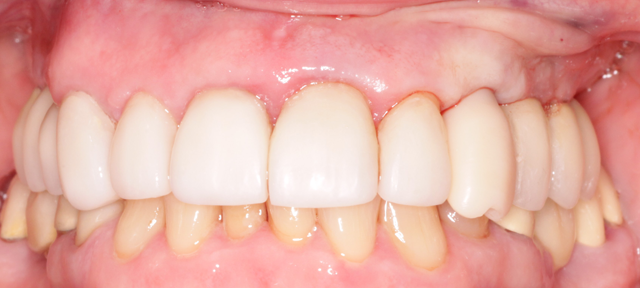

The Biohorizons custom milled temporary abutment and temporary custom PEEK crown were placed (Fig. 10). The gap between the implant and the extraction socket grafted with MinerOss, the occlusion adjusted and the soft tissue closed starting to contour the gingival tissues immediately.

Fig. 9 Fig. 10

This technique utilizes a digital workflow to provide initial implant planning, placement and esthetic sculpting of the gingival tissues. It affords the ability to start contouring an ideal emergence profile at the time of implant placement (Fig. 11).